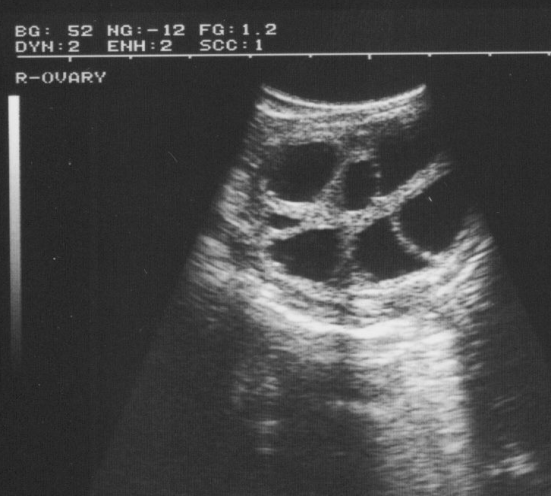

卵巢的超声评估应被视为生殖检查的常规部分,尤其是在牛身上。5MHz 换能器具有更高的分辨率,比 3 或 3.5MHz 换能器更适合评估卵巢。与其他流体结构一样,毛囊是无回声的,因此在超声图像上显示为黑色的外接结构,其形状为球形至不规则形状。不规则形状可归因于相邻卵泡和卵巢基质的黄体结构的压缩。

由上图可以看到小至 2 - 3 毫米的卵泡,通常可以在其整个功能寿命期间识别黄体估计发情周期的阶段,评估排卵前卵泡的状态和数量,确定排卵,监测黄体的发育和形态是卵巢超声检查的潜在应用之一。给定卵巢上卵泡的数量和大小会有很大差异,取决于一年中的时间和不同动物的生殖阶段。在早间期观察到许多小卵泡,这些卵泡在周期中期会变大。牛的优势卵泡或排卵卵泡将以每天 1.5 至 2.5 毫米的速度发育排卵前几天,这些都可以通过超声波轻松监测以确定排卵日期,从而确定适当的授精时间。在牛的发情周期中,优势卵泡的最大直径约为 10-20 毫米,最大的从属卵泡的最大直径约为 8 毫米。母牛在发情期结束后约 12 小时排卵。因此,授精时间可能在排卵前 6 到 24 小时之间。